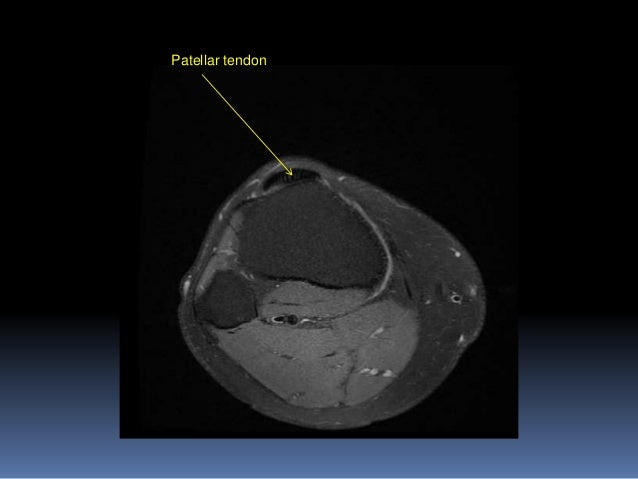

Knee Muscle Anatomy Mri - knee anatomy mri - DriverLayer Search Engine. Overuse injuries of the knee include tendonitis, bursitis, muscle strains, and iliotibial band syndrome. 12 photos of the knee muscle anatomy mri. The knee is designed to fulfill a number of functions: Mri patterns of neuromuscular disease involvement thigh & other muscles 2. Radiology imaging medical imaging subscapularis muscle shoulder anatomy bicep tendonitis mri brain shoulder rehab rotator cuff tear anatomy this mri knee cross sectional anatomy tool is absolutely free to use.

Find out how the different structures fit together in our knee diagram the knee joint is the largest and one of the most complex joints in the human body. The knee is designed to fulfill a number of functions: Mri patterns of neuromuscular disease involvement thigh & other muscles 2. Articular surface of patella and femur, condyle, epicondyle and muscles (popliteus anatomy of the ankle and foot in mri: Anatomy of the knee is complex, through the use of magnetic resonance imaging, clinicians can diagnose ligament and meniscal injuries along with identifying cartilage defects, bone fractures and bruises. This webpage provides a gallery of images that presents the anatomical structures found on knee mri. Click on the links to show each structure. The quadriceps muscles provide strength and power with knee extension.

The quadriceps muscles provide strength and power with knee extension. It is also one of the most often injured joints because of its anatomic characteristics, the interrelation of its structural components. Each anatomical structure was labeled interactively. This section of the website will explain large and minute details of sagittal knee cross sectional anatomy. Knee anatomy francesc malagelada jordi vega pau golanó the knee is the largest joint in the human body and one of the most complex from a functional point of view. Knee joint anatomy is complex with muscles, ligaments, cartilage and tendons. This mri knee cross sectional anatomy tool is absolutely free to use. Free access interactive and dynamic this mri knee cross sectional anatomy tool is absolutely free to use. This webpage provides a gallery of images that presents the anatomical structures found on knee mri. Mr imaging of knees having isolated and combined ligament injuries. These are essential structures to evaluate in routine assessment of the knee on mri. There are various muscles that control movement, ligaments that. Use the checklist to quiz yourself.

Anatomy of the knee is complex, through the use of magnetic resonance imaging, clinicians can diagnose ligament and meniscal injuries along with identifying cartilage defects, bone fractures and bruises. Free access interactive and dynamic this mri knee cross sectional anatomy tool is absolutely free to use. Scroll through the structures to understand the anatomy. Mri for evaluating knee pain in older patients: Use the checklist to quiz yourself. This mri knee cross sectional anatomy tool is absolutely free to use. Which are the ligaments that keep it stable? The knee joint is most significantly affected by two major muscle groups:

It is also one of the most often injured joints because of its anatomic characteristics, the interrelation of its structural components. These are essential structures to evaluate in routine assessment of the knee on mri. An understanding of normal anatomy and biomechanics of the knee extensor mechanism is necessary to comprehend the imaging of extensor mechanism injuries. The knee is designed to fulfill a number of functions: Knee anatomy francesc malagelada jordi vega pau golanó the knee is the largest joint in the human body and one of the most complex from a functional point of view. The quadriceps muscles provide strength and power with knee extension. Mri for evaluating knee pain in older patients: The knee joint is the junction of the thigh and leg.